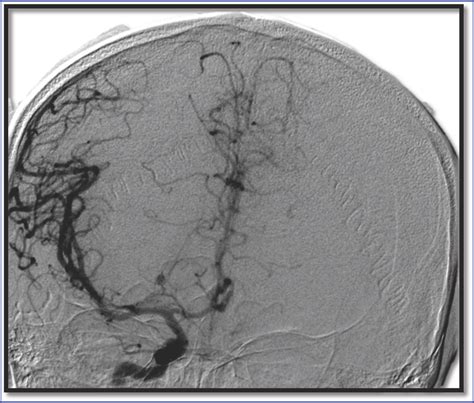

Because these aneurysms are microscopic, they differ significantly from berry aneurysms, which occur in larger cerebral arteries and can often be visualized using angiography. The inability to screen for these directly makes the prevention of their formation through blood pressure management the only viable strategy.

Diagnosing these aneurysms *before* they rupture is currently impossible with conventional clinical diagnostic imaging. Standard MRI and CT scans are designed to detect larger vascular abnormalities or tumors. A Charcot Bouchard aneurysm is essentially invisible on these scans due to its minute size. Diagnostic efforts are instead focused on identifying the consequences of these aneurysms, such as detecting small, asymptomatic bleeds (microbleeds) on specialized MRI sequences known as susceptibility-weighted imaging (SWI) or gradient-recalled echo (GRE).

• charcot bouchard aneurysm radiology